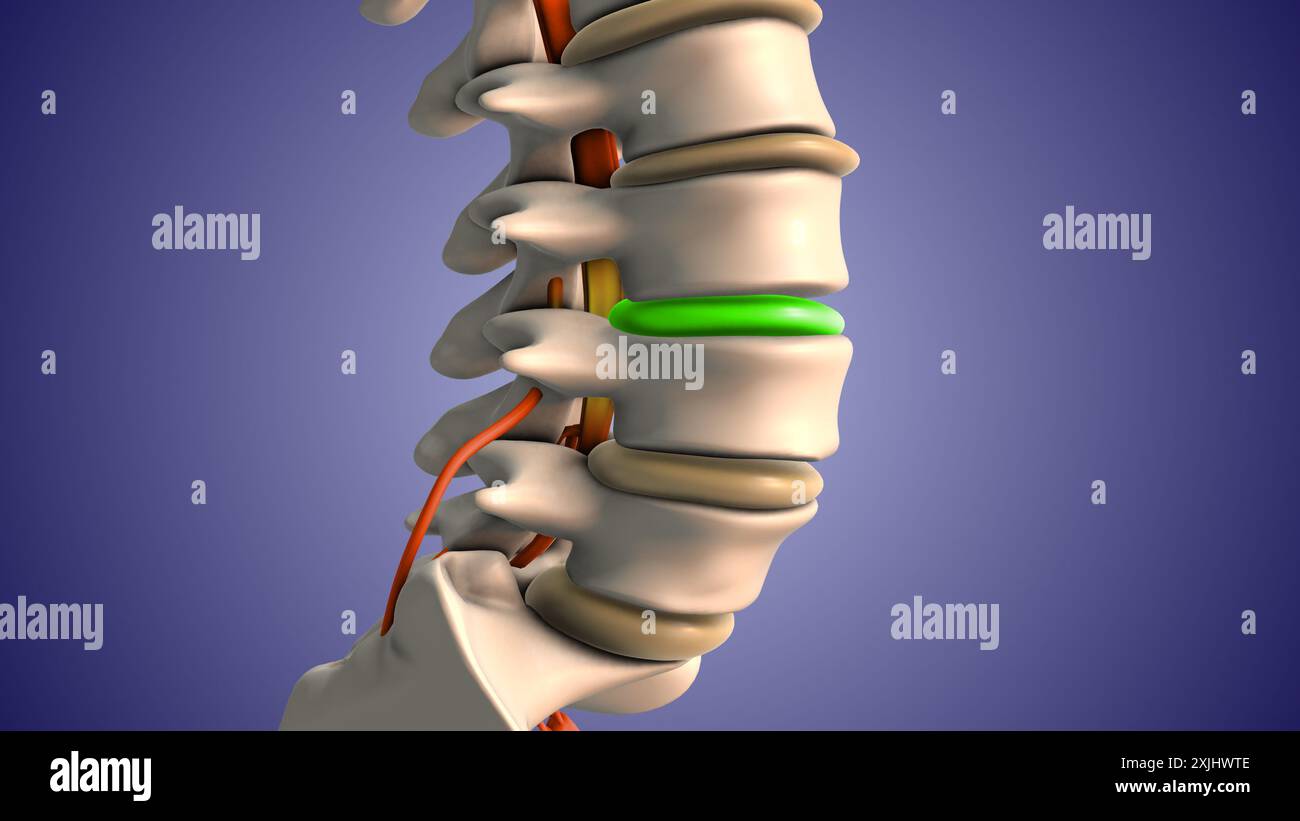

Ischiasnervenschmerz durch Bandscheibenvorfall Stockfotohttps://www.alamy.de/image-license-details/?v=1https://www.alamy.de/ischiasnervenschmerz-durch-bandscheibenvorfall-image613820161.html

Ischiasnervenschmerz durch Bandscheibenvorfall Stockfotohttps://www.alamy.de/image-license-details/?v=1https://www.alamy.de/ischiasnervenschmerz-durch-bandscheibenvorfall-image613820161.htmlRF2XJHWTH–Ischiasnervenschmerz durch Bandscheibenvorfall